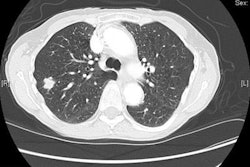

For individualized tumor therapy, Diedrich wrote that imaging is decisive when it comes to pre-treatment choices, such as with chemotherapy, radiation, or both, as well as predicting success and follow-up.

"With methods such as perfusion CT and MRI, measurement of the apparent diffusion coefficent value or PET-CT, it is possible to make a statement very early, after a week or, in the best case, after one day, whether the tumor responds to therapy," he added.